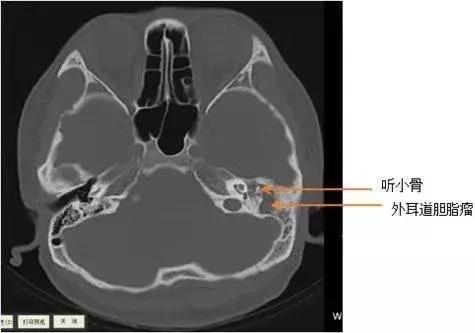

不出所料,颞骨CT检查显示小林左侧外耳道胆脂瘤,已挤压破坏左侧听骨链,且与左侧颈静脉及面神经管等重要结构关系密切,所以小林疼痛症状明显,左耳听力已有明显的下降。

ct片